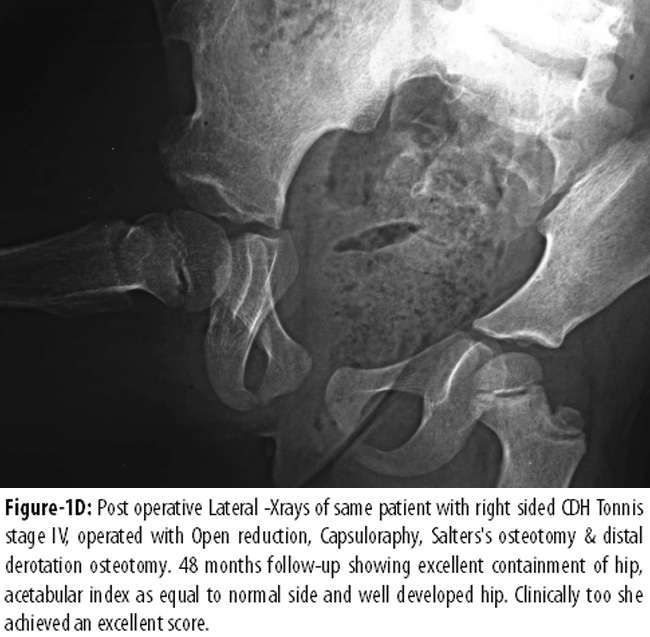

Figure-1CD appreciates the excellent containment, acetabular index 18° equal to normal side and development of the hip at four-year follow-up.

The successful treatment of CDH depends on concentric initial reduction, its maintenance in a stable position without interference of the blood supply, and an ultimately good remodelling of the hip.7 The results of CDH treatment are directly proportional to the age at the time of initial treatment.9 Treatment of CDH for these late-presenting children of walking age and older is a challenge, as closed or open reduction alone has not proven efficient in achieving successful results. Literature emphasises on additional procedures of femoral and pelvic osteotomy due to soft tissue contractures and structural abnormalities leading to subsequent dysplasia or subluxation. A high rate of very good results are reported with addition of pelvic or femoral osteotomies to open reduction.4,6,11,16,17 One study6 reported 86% clinical and 85% radiological excellent to good results in 23 hips in the age group from 1 year to 4 years treated with open reduction combined with femoral and/or pelvic osteotomies. One study,17 in its small series of 9 hips in 8 patients of similar age group carried out the procedure of simultaneous open reduction and Salter innominate osteotomy, which reported nearly similar 88.88% excellent results. Whereas one study18 reported little less; 77% clinical and 73% radiological good results in 33 hips of 25 older children with similar combined procedure. However, another study4 reported 100% clinical and 92% radiological good to excellent results in age group of 12 to 36 months. It combined Pemberton osteotomy (55%) when the anterolateral coverage of the femoral head was inadequate preoperatively, femoral derotation in 85% and femoral shortening in 4% cases. Similar one-stage combined procedures in same age groups like that study4 were adopted in the current study. However, our results were a little less than others,4,6,17 but nearly similar to some others.12,18,19 We have tried our best in surgery to avoid causing damage to vascularity, labrum and to reduce hip without enforcing tightness or pressure on the femoral head as has been advised in literature.19 Hence, we did not find significant AVN except in one. One study19 based on 1-55 months age group reported that spontaneous development of deep acetabulum can be achieved if the femoral head is maintained in centric reduction without abnormal pressure at any point and by avoiding frequent surgeries to construct the shelf. This, the study said, would allow the nature to play its role in the development of deep acetabulum around the 12th year of age. By this age, Morrison\'s epiphysis appears at the superior and posterior rim of the acetabulum.19 Our study shows the spontaneous mutual growth-stimulating effect of concentric reduction (Figure-1C). Another study12 compared results in various age groups and indicated progressively deteriorating results with increasing age i.e. with addition of every two years at presentation. It reported in a classical review based on long term follow-up, considering age at operation as a significant prognostic factor, 94% acceptable radiological results in younger (<2 years age) children, 80% in age group 2-4 years and 71% acceptable results in children >4 years age and lower incidence of AVN and late growth disturbance in age group <2 years. We always operate bilateral CDH under single anaesthesia to minimise hospitalisation, psychological impact on patient/parents, expenditure and use of medicine (Figure-2). A transfixation K-wire 1.5mm was used to stabilise femoral head in the true acetabulum in almost every hip and a DCP to osteosynthesis proximal femoral osteotomy in children over 30 months of age. Similar to literature20 we did not find any deleterious effect of K-wire as well with DCP in a single case (Figures-1, 2). The other important finding in this study was rapid development of caput femoris epiphysis which had not yet appeared at the time of surgery in the three youngest children and similar was the observation of an earlier study.21 The one-stage combined procedures in older age group reported earlier2,3,7,9,10,22 and others in younger age groups4,7,12,19 revealed clinically better results than radiological. It has been emphasised and concluded by these reports that what looks odd on X-ray i.e. superio-lateral acetabular irregularity (Figure-1C, D and 2C), has no significant bearing on clinical results. Till re-subluxation and AVN development, premature epiphyseal fusion, which leads to short femoral neck and partially uncovered femoral head due to less effective development of acetabulum, as seen in our two cases, have been reported previously.9,12 This acetabular irregularity, as noticed in our previous reports,9,10 has been known to disappear with well-contoured acetabulum on >10 years follow-up.19 Two hips in this study that went to re-subluxations, where one of them was associated with AVN, had no pelvic osteotomy at primary procedure. They required secondary procedure of Salters osteotomy. This further supports the claim of addition of pelvis osteotomy, especially in those hips that have stable hip on Catteral\'s test of stability,12 in position of flexion, abduction and internal rotation. Both the hips achieved good overall rating with recovery from AVN with coxa megna and comparable wide acetabulum on long term follow-up of 5 and 6 years. One case in this study had bilateral dislocation, Tonnis stage IV, and was operated with open reduction, capsuloraphy and Salter\'s osteotomy which developed re-subluxation Tonnis III stage on the left side. Five months after surgery, this patient was re-operated with capsuloraphy, Salter\'s osteotomy and distal derotation osteotomy at age 27 months that did not achieve the desired result. Therefore, she needed another operation with proximal derotation osteotomy and Chiari\'s displacement osteotomy at the age of 5 years. By this time she was diagnosed on re-evaluation to have hyperlaxity syndrome which had not been diagnosed earlier. This girl at seven years follow-up (age 9.5 years) had excellent hip on the right side, but had clinical score fair and radiological rating good on the left side. At 7.5-year follow-up she still walks with hyperlordosis, squats with support, and has developed bilateral pes-plano valgus deformity as well. However, her hips are contained well.